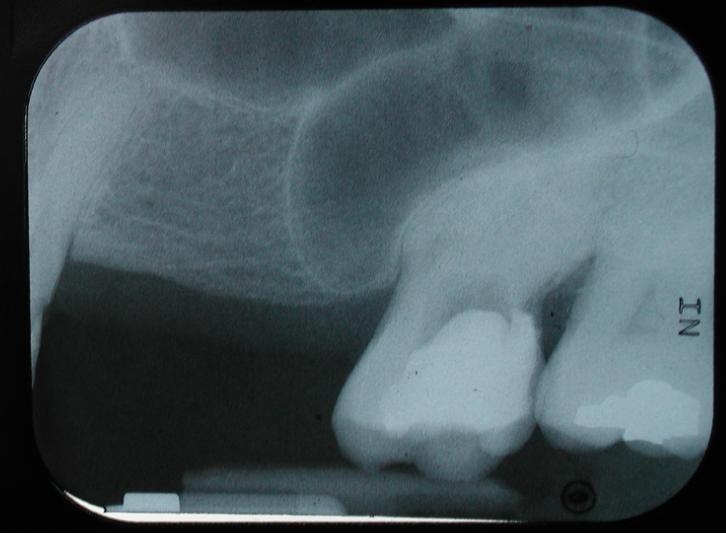

바닥은 치조돌기에 의해 형성된다. 위턱굴의 크기가 평균적일 경우, 바닥은 코 바닥과 같은 높이에 위치한다. 굴이 크면 이 높이보다 아래에 위치할 수도 있다. 위턱굴 바닥으로 돌출된 몇 개의 원뿔 모양 돌기는 첫 번째 및 두 번째 위턱 어금니의 뿌리에 해당한다. 어떤 경우에는 치아 뿌리 끝부분이 위턱굴 바닥을 뚫고 들어가기도 한다.

성인의 위턱굴 크기는 사람마다 다르며, 클 경우에는 위턱뼈의 관골 돌기와 이틀 돌기까지 확장될 수 있다.[3]위턱굴이 이틀 돌기까지 확장되면 어금니나 작은어금니의 뿌리가 위턱굴 바닥 바로 아래에 위치하거나, 심지어 바닥을 뚫고 위턱굴 안으로 돌출될 수 있다. 이런 경우 치아 뿌리는 보통 얇은 뼈로 덮여 있지만, 때로는 위턱굴의 점막 바로 아래에 놓이기도 한다. 특히 나이가 들면서 뼈 흡수가 일어나면 치아 뿌리가 위턱굴로 돌출되는 경우가 더 흔해진다.[3] 이러한 상태에서 치아를 뽑으면 구강과 위턱굴 사이에 구멍(누공)이 생길 수 있지만, 대부분 자연적으로 아물게 된다.[3]

상악동 부비동염은 위턱굴, 즉 상악동에 생긴 염증을 말한다. 부비동염의 주요 증상으로는 염증이 생긴 부위 근처의 두통, 불쾌한 냄새가 나는 코나 목 분비물, 발열, 전신 쇠약감 등이 나타날 수 있다. 염증이 있는 부위의 피부는 만지면 아프거나(압통), 열감이 느껴지거나, 붉어지기도 한다. 방사선 사진을 찍어보면 정상적으로 공기가 차 있어 검게 보여야 할 상악동이 염증으로 인한 점액 저류 때문에 불투명하게 보이거나 뿌옇게 나타난다.[7]

위턱 뒤쪽 치아의 뿌리와 상악동 바닥 사이에는 항상 슈나이더 막 (Schneiderian membrane)이라는 얇은 점막층이 있으며, 대부분의 경우 뼈도 존재한다. 그러나 이 뼈의 두께는 사람마다 매우 달라서, 뼈가 전혀 없는 경우부터 12mm 두께에 이르기까지 다양하다.[9] 따라서 치아를 발치할 때 상악동의 막이나 뼈 바닥이 천공되어 구강으로 통하는 구멍, 즉 OAC가 생길 수 있다.[10]